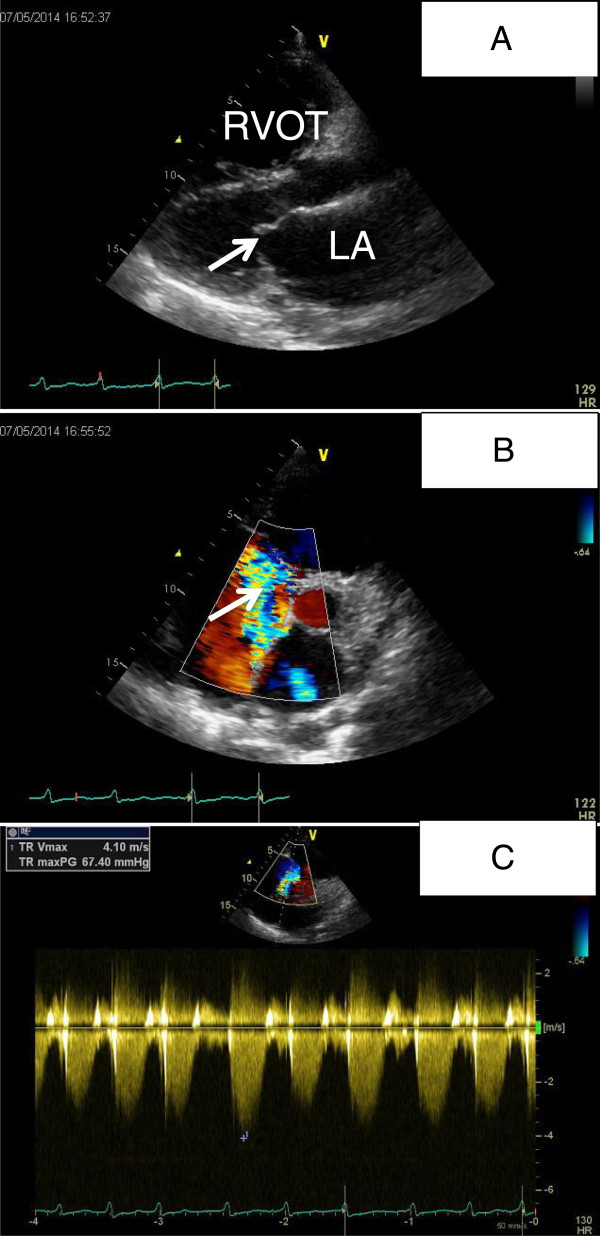

On admission the patient’s blood pressure was 121/68 mmHg, heart rate was around 110 bpm and irregular. The jugular veins were distended. Cardiac examination revealed an irregular tachycardia and a systolic apical murmur of grade 2/6. Rales were heard over the left lung base. The liver edge was palpable below the costal margin with tender. Edema was present in the both lower extremities. Laboratory tests revealed unremarkable findings except for the reduced blood oxygen pressure of 57 mmHg. Electrocardiogram showed atrial fibrillation and evidence of right ventricular hypertrophy. Transthoracic echocardiography (TTE) showed PAH with the estimated pulmonary arterial systolic pressure of 77 mmHg and dilatation of the right ventricle (RV) and right atrium (RA) (Figure 1A, B, C). Transesophageal echocardiography (TEE) was unable to complete successfully.

Figure 1.

TTE revealed PAH with right-sided chamber enlargement. A: Dilatation of the RVOT(right ventricular outflow tract) was shown. B: Severe tricuspid regurgitation was shown in the parasternal short axis view (white arrow) with dilatation of RV and RA. C: The pressure gradient between the RV and RA was around 67 mmHg by measuring the tricuspid regurgitation Doppler jet.